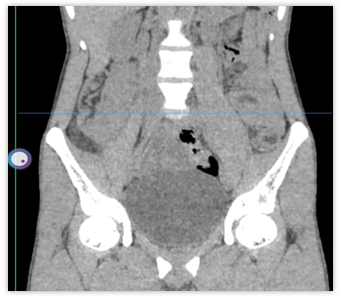

We report here a case of a 21 y old male patient who presented to the casualty with complaints of severe abdominal pain, nausea, vomiting, and loose motion for the past week. Upon a general physical examination, the patient had a slightly increased fever, tachycardia, and short, frequent breaths. On local examination, the abdomen was mildly distended and tender, with the presence of voluntary guarding on palpation. No mass was palpated per abdomen. Tenderness was more prominent on the right side. On digital rectal examination, no palpable mass was felt, and the glove was stained with reddish-yellow fecal matter. The patient was immediately admitted and kept NPO until further order; a 16-fr RT was inserted with continuous aspiration; and a 16-fr Foley’s catheter was connected to monitor the urine output. Intravenous fluid was started, and a prophylactic 3rd-generation cephalosporin was started along with injectable metronidazole, proton pump inhibitors, and analgesics. A complete blood hemogram and an ultrasonography of the abdomen were advised for the initial assessment. Ultrasonography of the abdomen and pelvis showed concentric rings of bowel loops in the right iliac fossa, suggestive of ilio-colic intussuption with no proximal dilation of bowel loops. There is symmetrical mural thickening of the bowel wall of the ascending colon with few sub-centimetric lymphnodes around the right iliac fossa. In view of the above, a CT scan of the whole abdomen (fig. 1A and 1B) was advised, which suggested subacute intestinal obstruction with large Ileo-colic intussusception with 3.5 x 3.0 cm of soft tissue as the lead point.

Fig. 1A and 1B: Photograph showing SAIO with large Ileo-colic intussusception with a 3.5 x 3.0 cm soft tissue as the lead point]